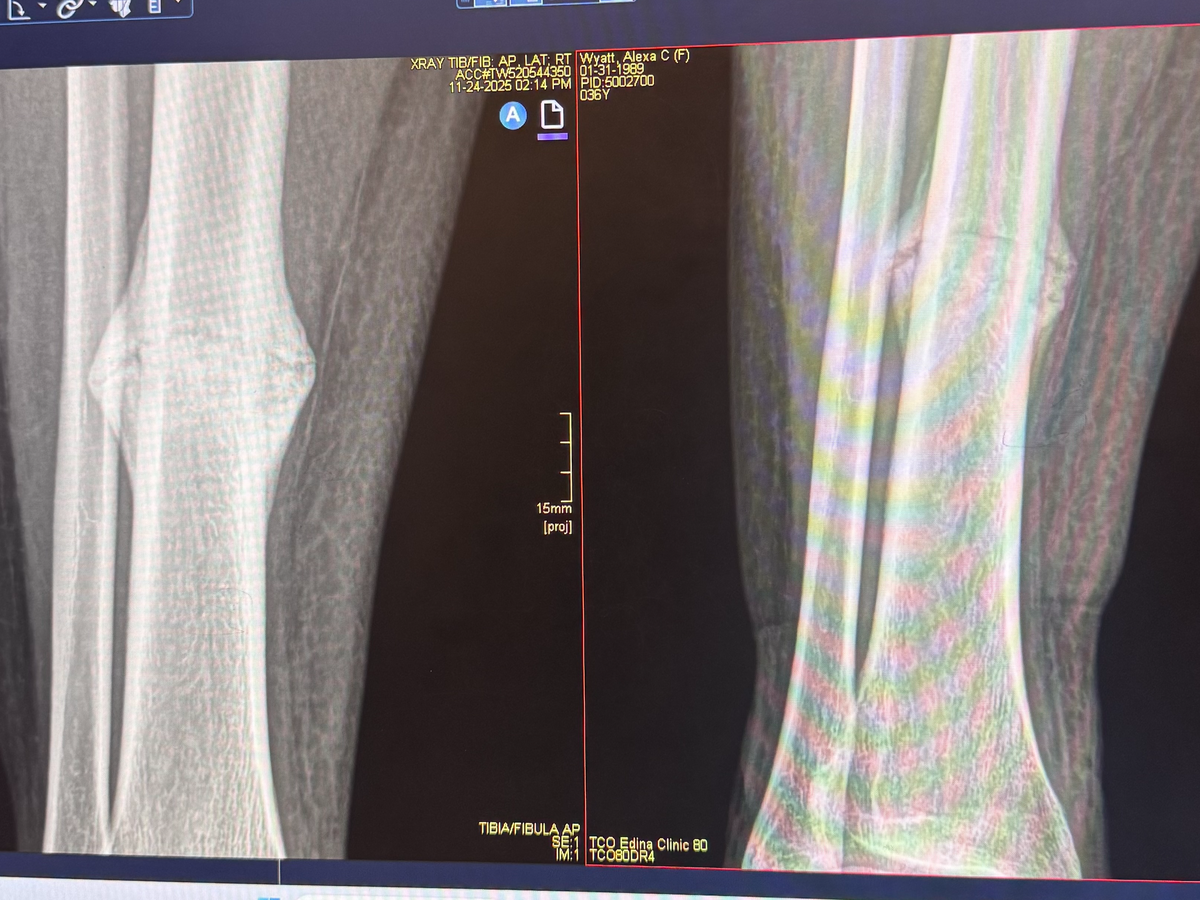

My name is Jessica, and I am Alexa’s partner. In July, Alexa suffered a tibial fracture that has significantly affected her mobility and ability to work. Over the past five months, she has pursued every recommended non-surgical treatment option in hopes of healing naturally. Unfortunately, medical evaluation has now confirmed that surgery is necessary in order for her to properly heal.